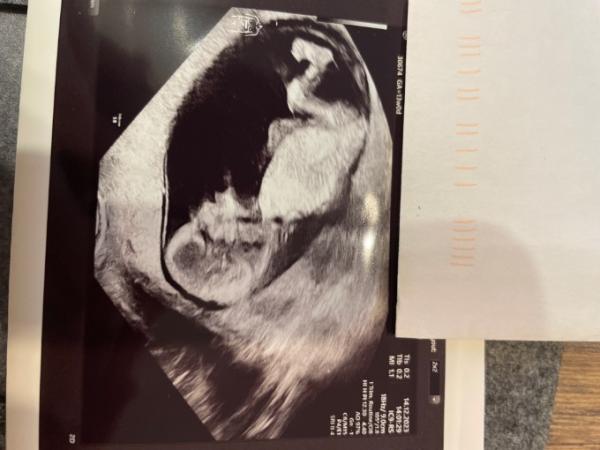

Herz, Nieren, Magen, Nabelschnur, Hirn und keine Ahnung was sie sonst noch alles sehen konnte ist super in Ordnung.

Krümelmonster ist 7,1cm

Nackenfalte hat 1,2mm

Nasenbein ist super entwickelt und sichtbar

Profil Nasenspitze zu Kinn konnte die nicht sehen da das Krümelmonster äußerst agil war im Ultraschall und sie jedes Mal froh war das Bild anhalten zu können